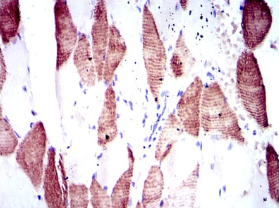

IHC    1/200 - 1/1000